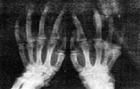

澱粉樣關節病體形變小,步伐僵硬,單側或雙側性脛股關節增大,有的脛跖關節變粗。

肝臟腫脹,呈青銅色;脾臟腫大、蒼白。剖開關節腔,可見淺層關節軟骨和關節囊周圍組織上有橘黃色物質沉積。